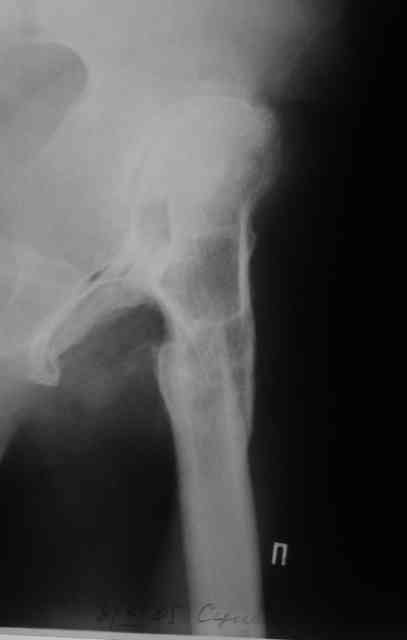

Уважаемый Андрей, ситуация не простая, нет обзорной Р-графии таза, поэтому сложно провести правильное планирование операции. Тем не менее, при планировании операции вертлужный компонент я бы установил в анатомическое положение. В отношении ножки - может быть два решения. Мое предпочтение - (операция типа Paavilaanen'a) поперечная остеотомия бедра на уровне чуть выше деформации, установка ножки Вагнера, скорее всего 190 мм, хотя возможно удастся обойтись и конической ножкой, это зависит от необходимой компенсации длины ноги. Продольная остеотомия б/вертела с последующей фиксацией к диафизу бедра с натяжением мышц. Есть и другой вариант - укорачивающая остеотомия в зоне деформации бедра с установкой ножки со стороны шейки. Мы делали и то и другое, первый вариант проще. В этой операции есть масса нюансов и нужно иметь опыт операций при дисплазии ТБС.

В прищепке случай 1999 года - эндопротезирование после операции Шанца-Илизарова. Возраст пациентки 45. Коррекция была в 17 лет. А Рыков Хабаровск.